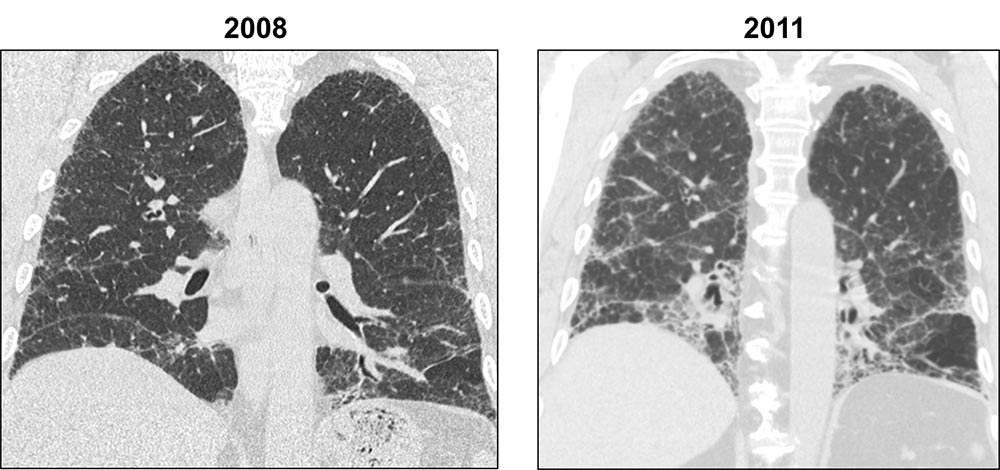

This series of axial HRCT images shows the progression of usual interstitial pneumonia (UIP) over time. The peripheral reticulation in the 2008 image has progressed to honeycombing over the 3 year time period, and prominent traction bronchiectasis is seen in the later image, a feature not seen previously.

Images courtesy of and used with permission from Sudhakar Pipavath, MD.